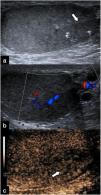

Contrast-enhanced ultrasound (CEUS) is an advanced technique that stands out for its ability to assess macrovascularisation and organ and tumour perfusion in situations where Doppler mode has limitations, such as small lesions, slow flow, or artifacts. These features make it a highly valuable tool for the accurate diagnosis of scrotal pathologies, especially in cases where determining the need for surgical intervention is critical. Additionally, CEUS is a safe and well-tolerated technique, applicable to virtually all patients, including the paediatric population. Its applications include managing testicular torsion, trauma, segmental infarctions, and focal lesions, as well as characterising tumours and evaluating complications such as abscesses and haematomas. This review aims to provide a guide on the use of CEUS in scrotal pathology, highlighting its clinical indications and advantages over conventional ultrasound.